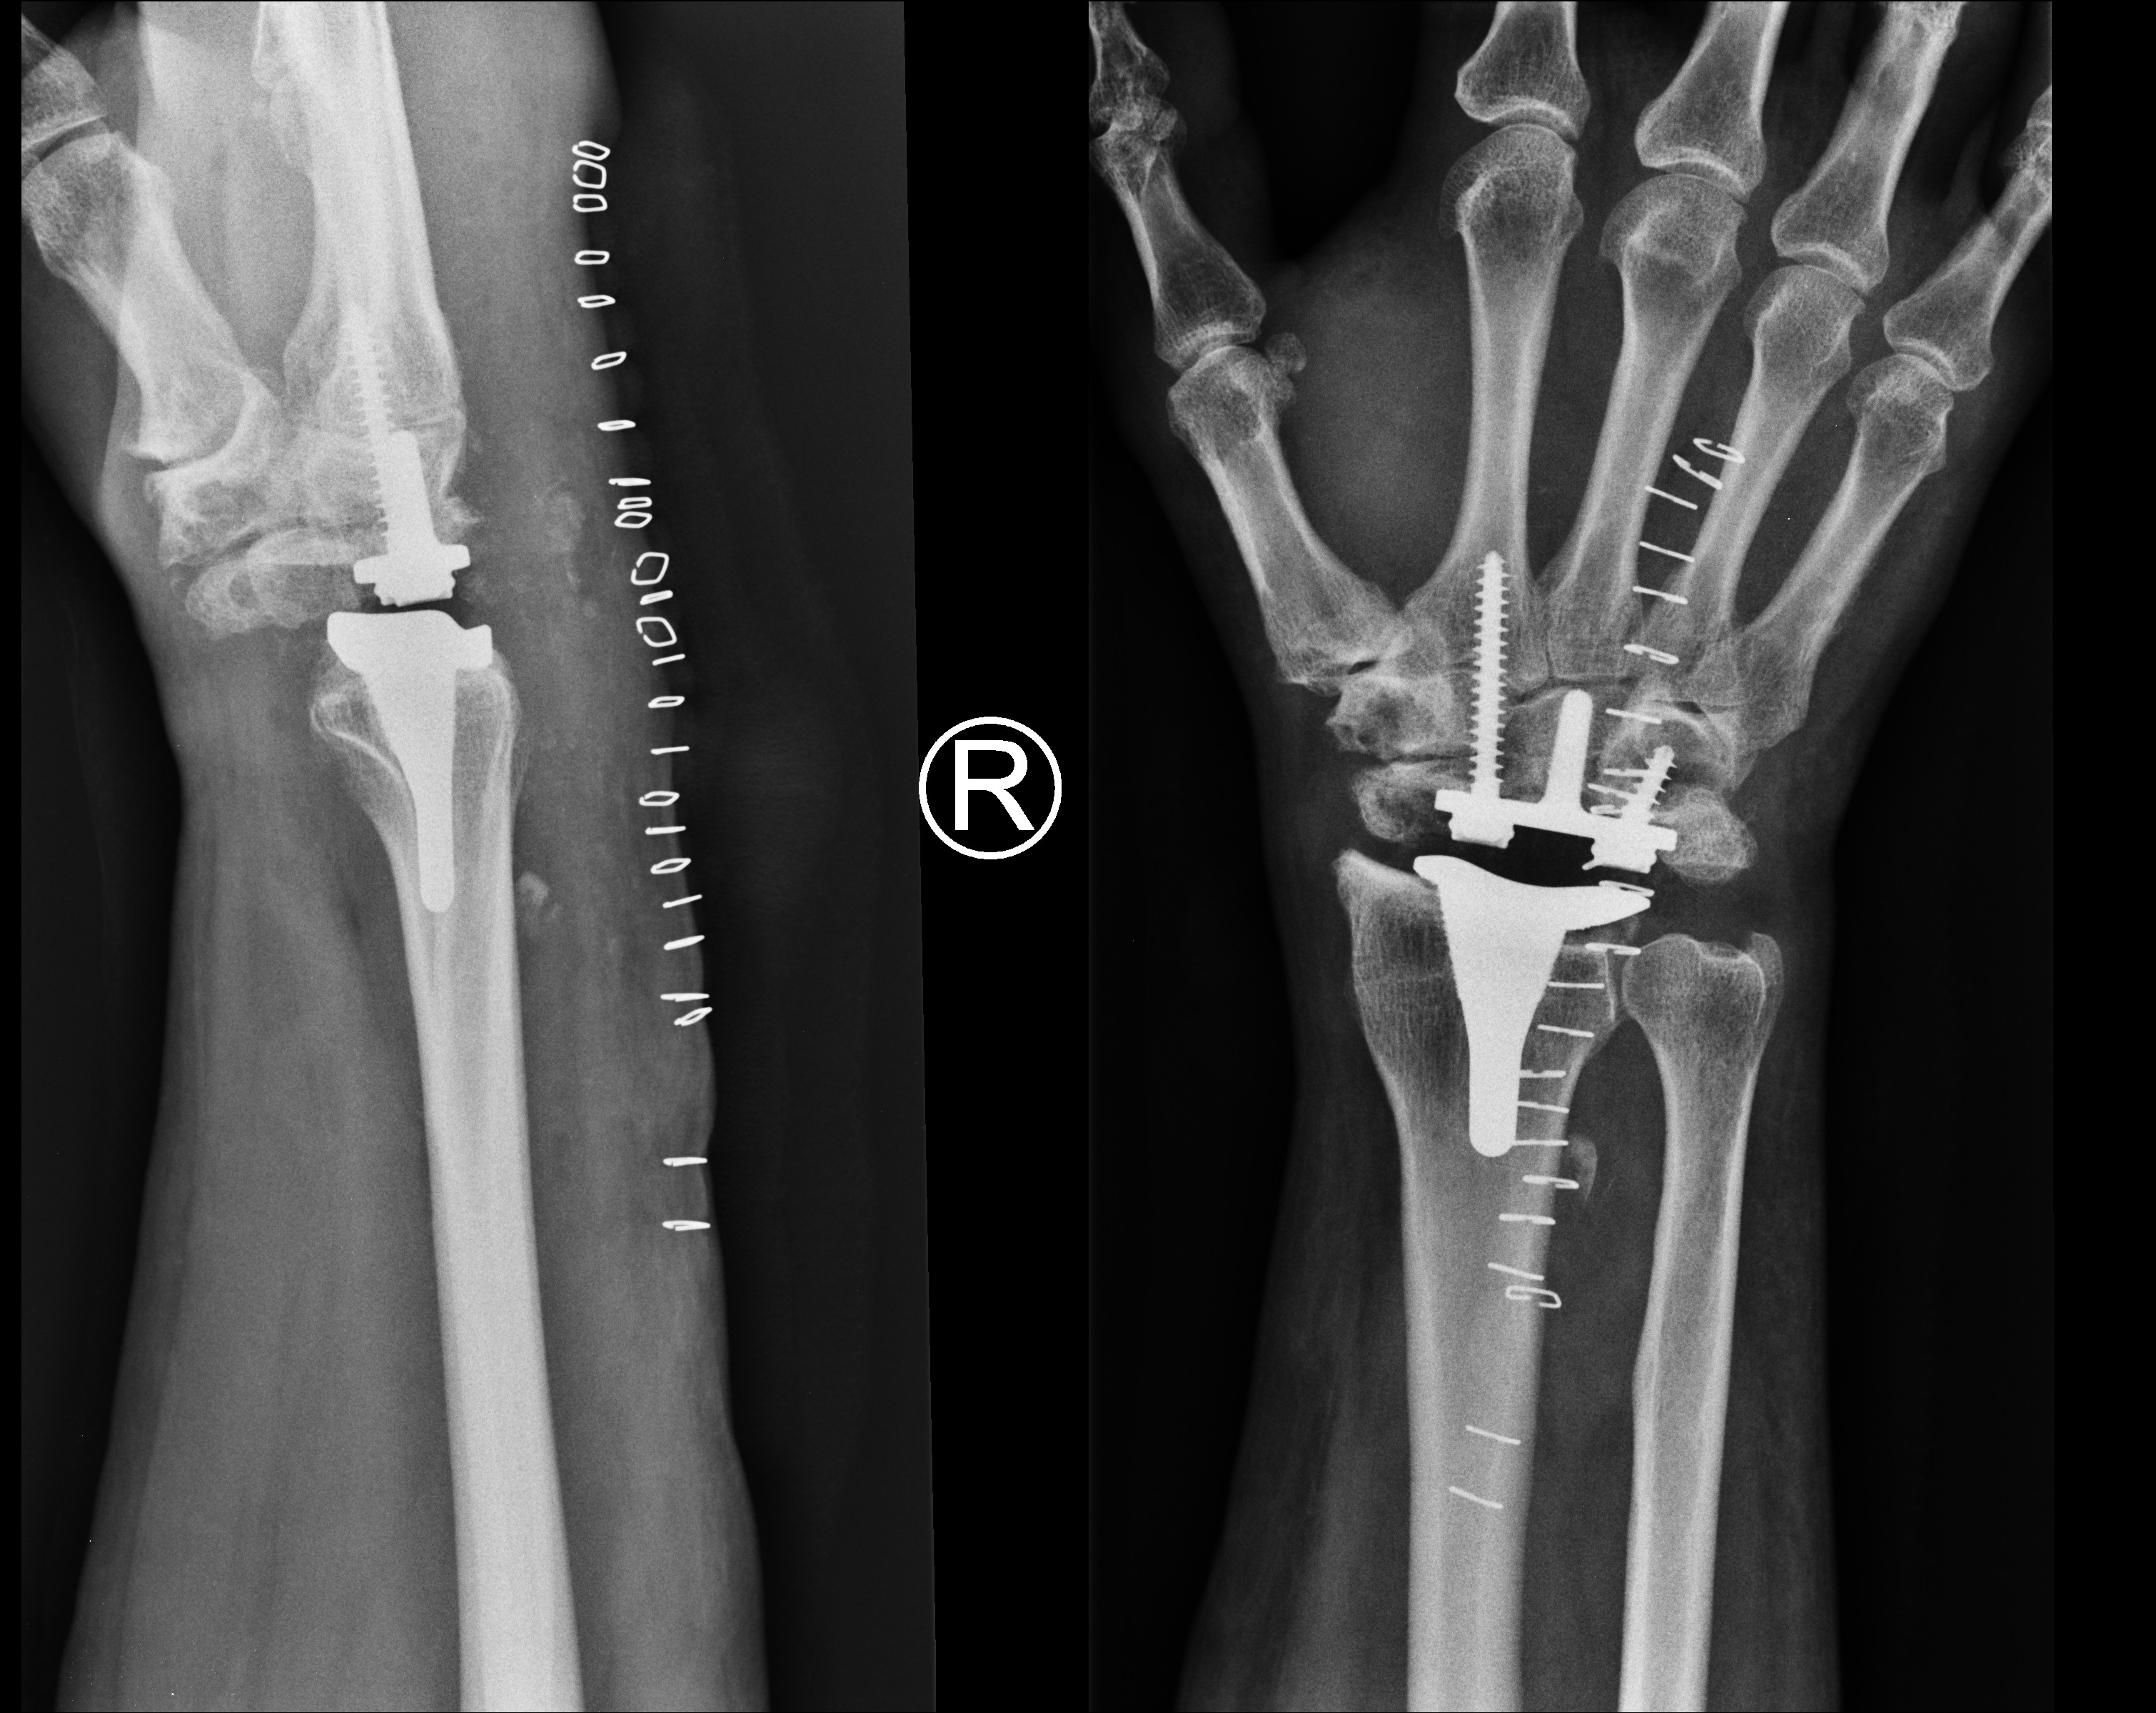

Z ogromną satysfakcją informuję, że w miesiącu listopadzie br. doktor Włodzimierz Witwicki wraz z zespołem, przeprowadził w buskim szpitalu bardzo trudny i rzadko wykonywany zabieg operacyjny endoprotezy nadgarstka – poinformował o sukcesie lekarzy ortopedów dyrektor ZOZ Grzegorz Lasak na e-stronie placówki.

U operowanego pacjenta w młodości doszło do urazu nadgarstka, co zaskutkowało zwyrodnieniem, objawiającym się blokadą ruchu oraz dużymi dolegliwościami bólowymi. Do wymiany stawu nadgarstka dochodzi wtedy, gdy leczenie farmakologiczne nie przynosi pozytywnych efektów.

Skutkiem przeprowadzonego zabiegu jest uwolnienie pacjenta od przejmującego bólu, widocznej gołym okiem opuchlizny, oraz usunięcie dolegliwości związanych ze sztywnością stawu. Przed zabiegiem, chory nie mógł wykonywać nawet prostych, podstawowych czynności typu: zapinanie odzieży na guziki, posługiwanie się kluczami itp. Dziś – po zabiegu – poprawie uległ komfort jego życia, a dolegliwości bólowe ustąpiły.

Warto podkreślić, że jest to pierwszy w Polsce zabieg, z wykorzystaniem konkretnej endoprotezy nadgarstka, renomowanej – amerykańskiej firmy (nazwy nie podajemy). Podobne zabiegi wykonywane są w naszym kraju wyłącznie na terenie specjalistycznych klinik.